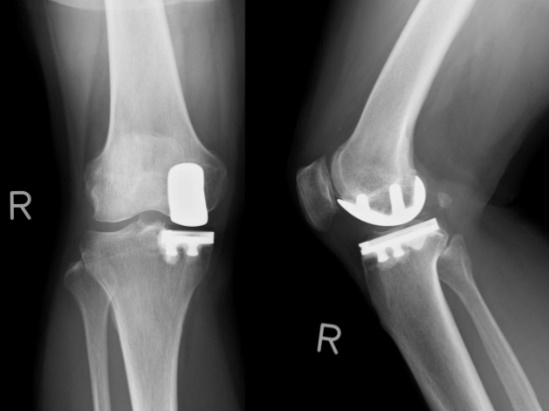

人工膝関節単顆置換術 (unicompartmental knee arthroplasty: UKA)

膝関節の内側もしくは外側のみの単顆型の変形や骨壊死症に適応があります。片側のみの人工関節置換術であることから、手術侵襲が少なく、術早期から除痛が得られ、歩行が可能となります。